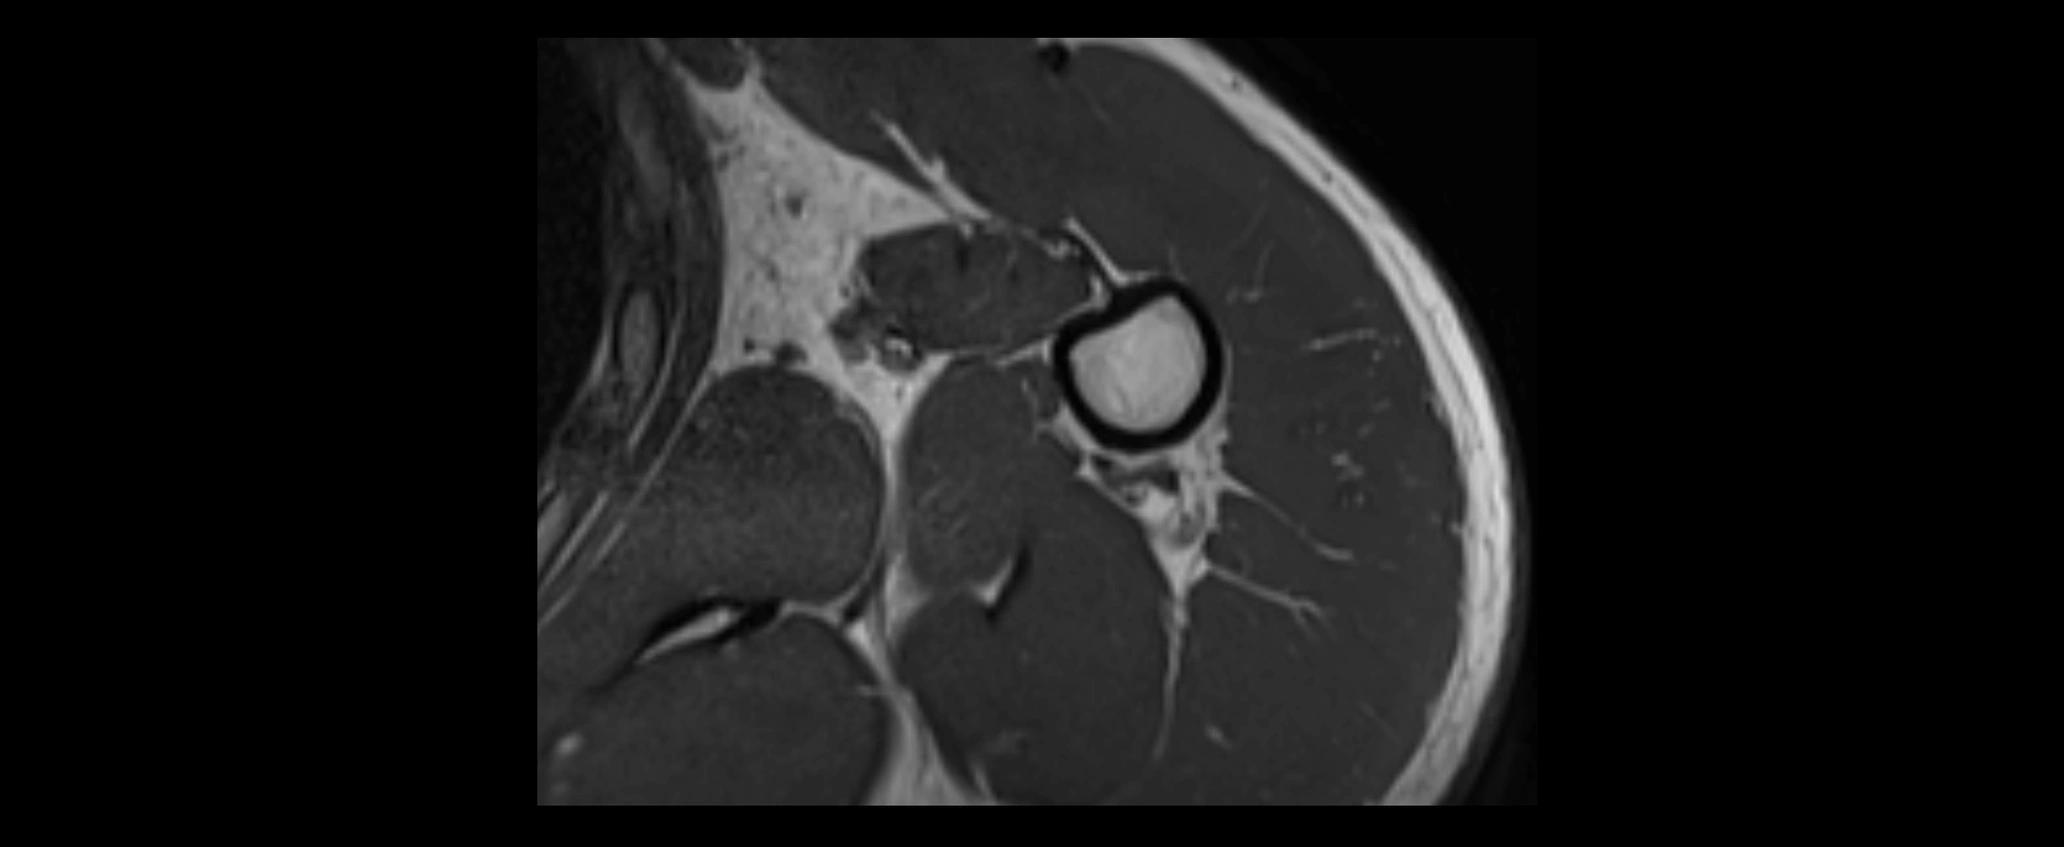

MRI images

image